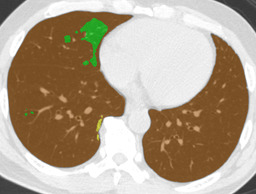

In this paper, we define partial annotation as an annotation format in which only one class is chosen for the annotation and only pixels belonging to the chosen class are annotated per image. For example, in Figure 1(a), although there is ground glass opacity in the image, only consolidation is chosen for annotation and pixels of consolidation are annotated. Partially annotated dataset is less informative for training, however, it is much easier to create compared to fully annotated dataset since annotators only need to focus on one class at a time during the annotation task.

Partially annotated datasets have been utilized previously [8, 9]. In this paper, we propose a new weak supervision technique that fully utilizes partially annotated dataset. Throughout this paper, each DLD pattern is represented or painted in the following colors (CON:cyan, GGO:yellow, HCM:red, EMP:green, NOR:brown.)

Statistics of our dataset are shown in Table 1 and typical images and their annotations for each DLD pattern are shown in Figure 1. In our partially annotated dataset, all the pixels in a slice were manually classified into two classes: dominating DLD pattern and other tissues. In other words, all the pixels in our dataset were assigned one of the labels from either of the two label sets, Lstrong={lCON,lGGO,lHCM,lEMP,lNOR}subscript𝐿𝑠𝑡𝑟𝑜𝑛𝑔subscript𝑙𝐶𝑂𝑁subscript𝑙𝐺𝐺𝑂subscript𝑙𝐻𝐶𝑀subscript𝑙𝐸𝑀𝑃subscript𝑙𝑁𝑂𝑅L_{strong}=\{l_{CON},l_{GGO},l_{HCM},l_{EMP},l_{NOR}\} or Lweak={lCON¯,lGGO¯,lHCM¯,lEMP¯,lNOR¯}subscript𝐿𝑤𝑒𝑎𝑘subscript𝑙¯𝐶𝑂𝑁subscript𝑙¯𝐺𝐺𝑂subscript𝑙¯𝐻𝐶𝑀subscript𝑙¯𝐸𝑀𝑃subscript𝑙¯𝑁𝑂𝑅L_{weak}=\{l_{\overline{CON}},l_{\overline{GGO}},l_{\overline{HCM}},l_{\overline{EMP}},l_{\overline{NOR}}\}. For example, in Figure 1(a), colored pixels were labeled as lCONsubscript𝑙𝐶𝑂𝑁l_{CON} and all the other pixels were labeled as lCON¯subscript𝑙¯𝐶𝑂𝑁l_{\overline{CON}}. In this paper, we call pixels of label lLweak𝑙subscript𝐿𝑤𝑒𝑎𝑘l\in L_{weak} and lLstrong𝑙subscript𝐿𝑠𝑡𝑟𝑜𝑛𝑔l\in L_{strong} as weakly annotated pixels and strongly annotated pixels respectively. Our pixel-wise annotations were created in the following steps. First, up to 3 slices were chosen for the annotation for each HRCT scan and for each slice, one representing DLD pattern was chosen by a radiologist. Second, three radiologists performed pixel-wise binary annotation (e.g. binary annotation between lCONsubscript𝑙𝐶𝑂𝑁l_{CON} or lCON¯subscript𝑙¯𝐶𝑂𝑁l_{\overline{CON}}) for each slice. Finally, the radiologists’ annotations were merged by taking majority classes for each pixel (i.e. pixels labeled as a DLD pattern by more than 2 radiologists became the corresponding DLD pixel). In addition to the DLDs annotation, lung fields were manually segmented under the supervision of radiologists and training and testing were conducted only within the lung fields.

Figure 1: Typical slices for each DLD classes. Slices of HRCT are shown in lung window setting (window-center=-600, window-width=1500) with annotated labels superimposed in transparent colors. Note that even if more than one DLD patterns existed, only one DLD pattern was chosen and annotated for a slice to facilitate the annotation process.